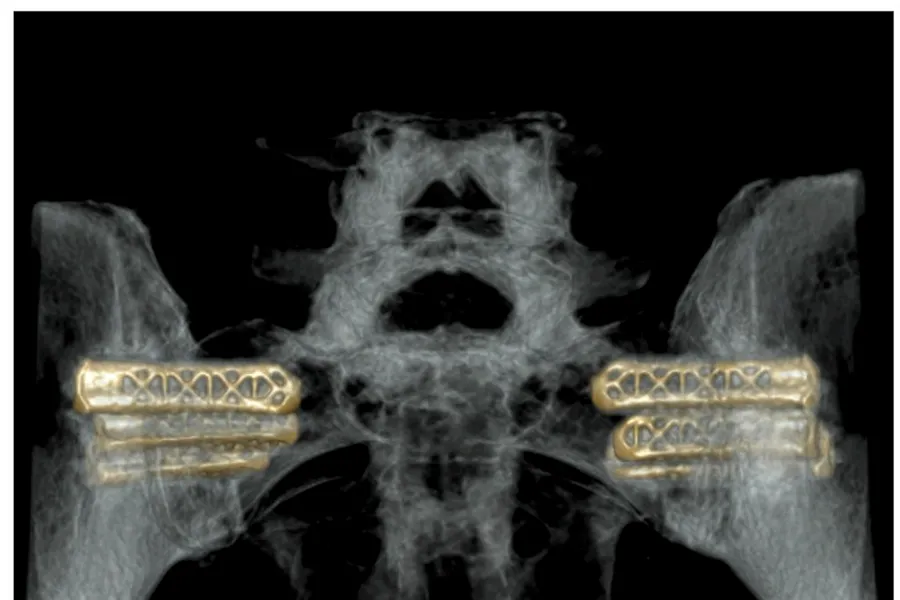

Foto: Courtesy of Radiologisk avdeling, Oslo universitetssykehus (OUS), Rikshospitalet.

Når en skal stive av bekkenleddet lages det et lite snitt i huden og det settes inn to eller tre implantater som stiver av bekkenleddet bak. Det fantes to tidligere forskningsprosjekter som viste at denne typen inngrep hadde god effekt på å redusere smerter og bedre funksjonsevnen.